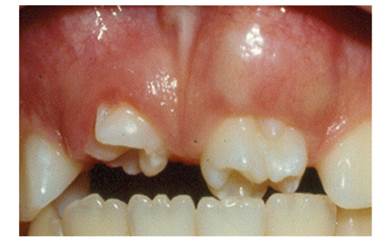

Figure 3, Figure 4, Figure 5 and Figure 6 show the clinical images and x-ray image of a 10-year-old male patient who consulted the Emergency Clinic of Universidad del Valle School of Dentistry. They show two large molariform teeth in the upper anterior region in between the lateral incisors. The radiograph shows that the upper right mesiodens has moved the right central incisor to the region of the lateral right, and the left upper mesiodens is blocking the eruption of the left central incisor.

Note the presence of two molariform mesiodens blocking eruption of the upper central incisors.

In case 2, the molariform mesiodens were blocking the eruption of permanent incisors, agreeing with what has been reported in the literature,32)(33) affecting the room available for teeth in the upper anterior segment. In case 3, the conical mesiodens allowed the eruption of permanent central incisors with lateral displacement, as previously reported.2)(13